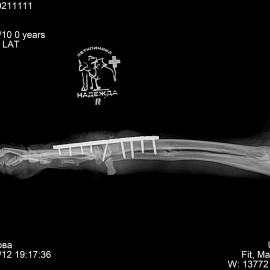

Снимок 1 перелом фаланг пальцев правой плюсны (задней лапы).

Снимок 4 после операции на запястном суставе.